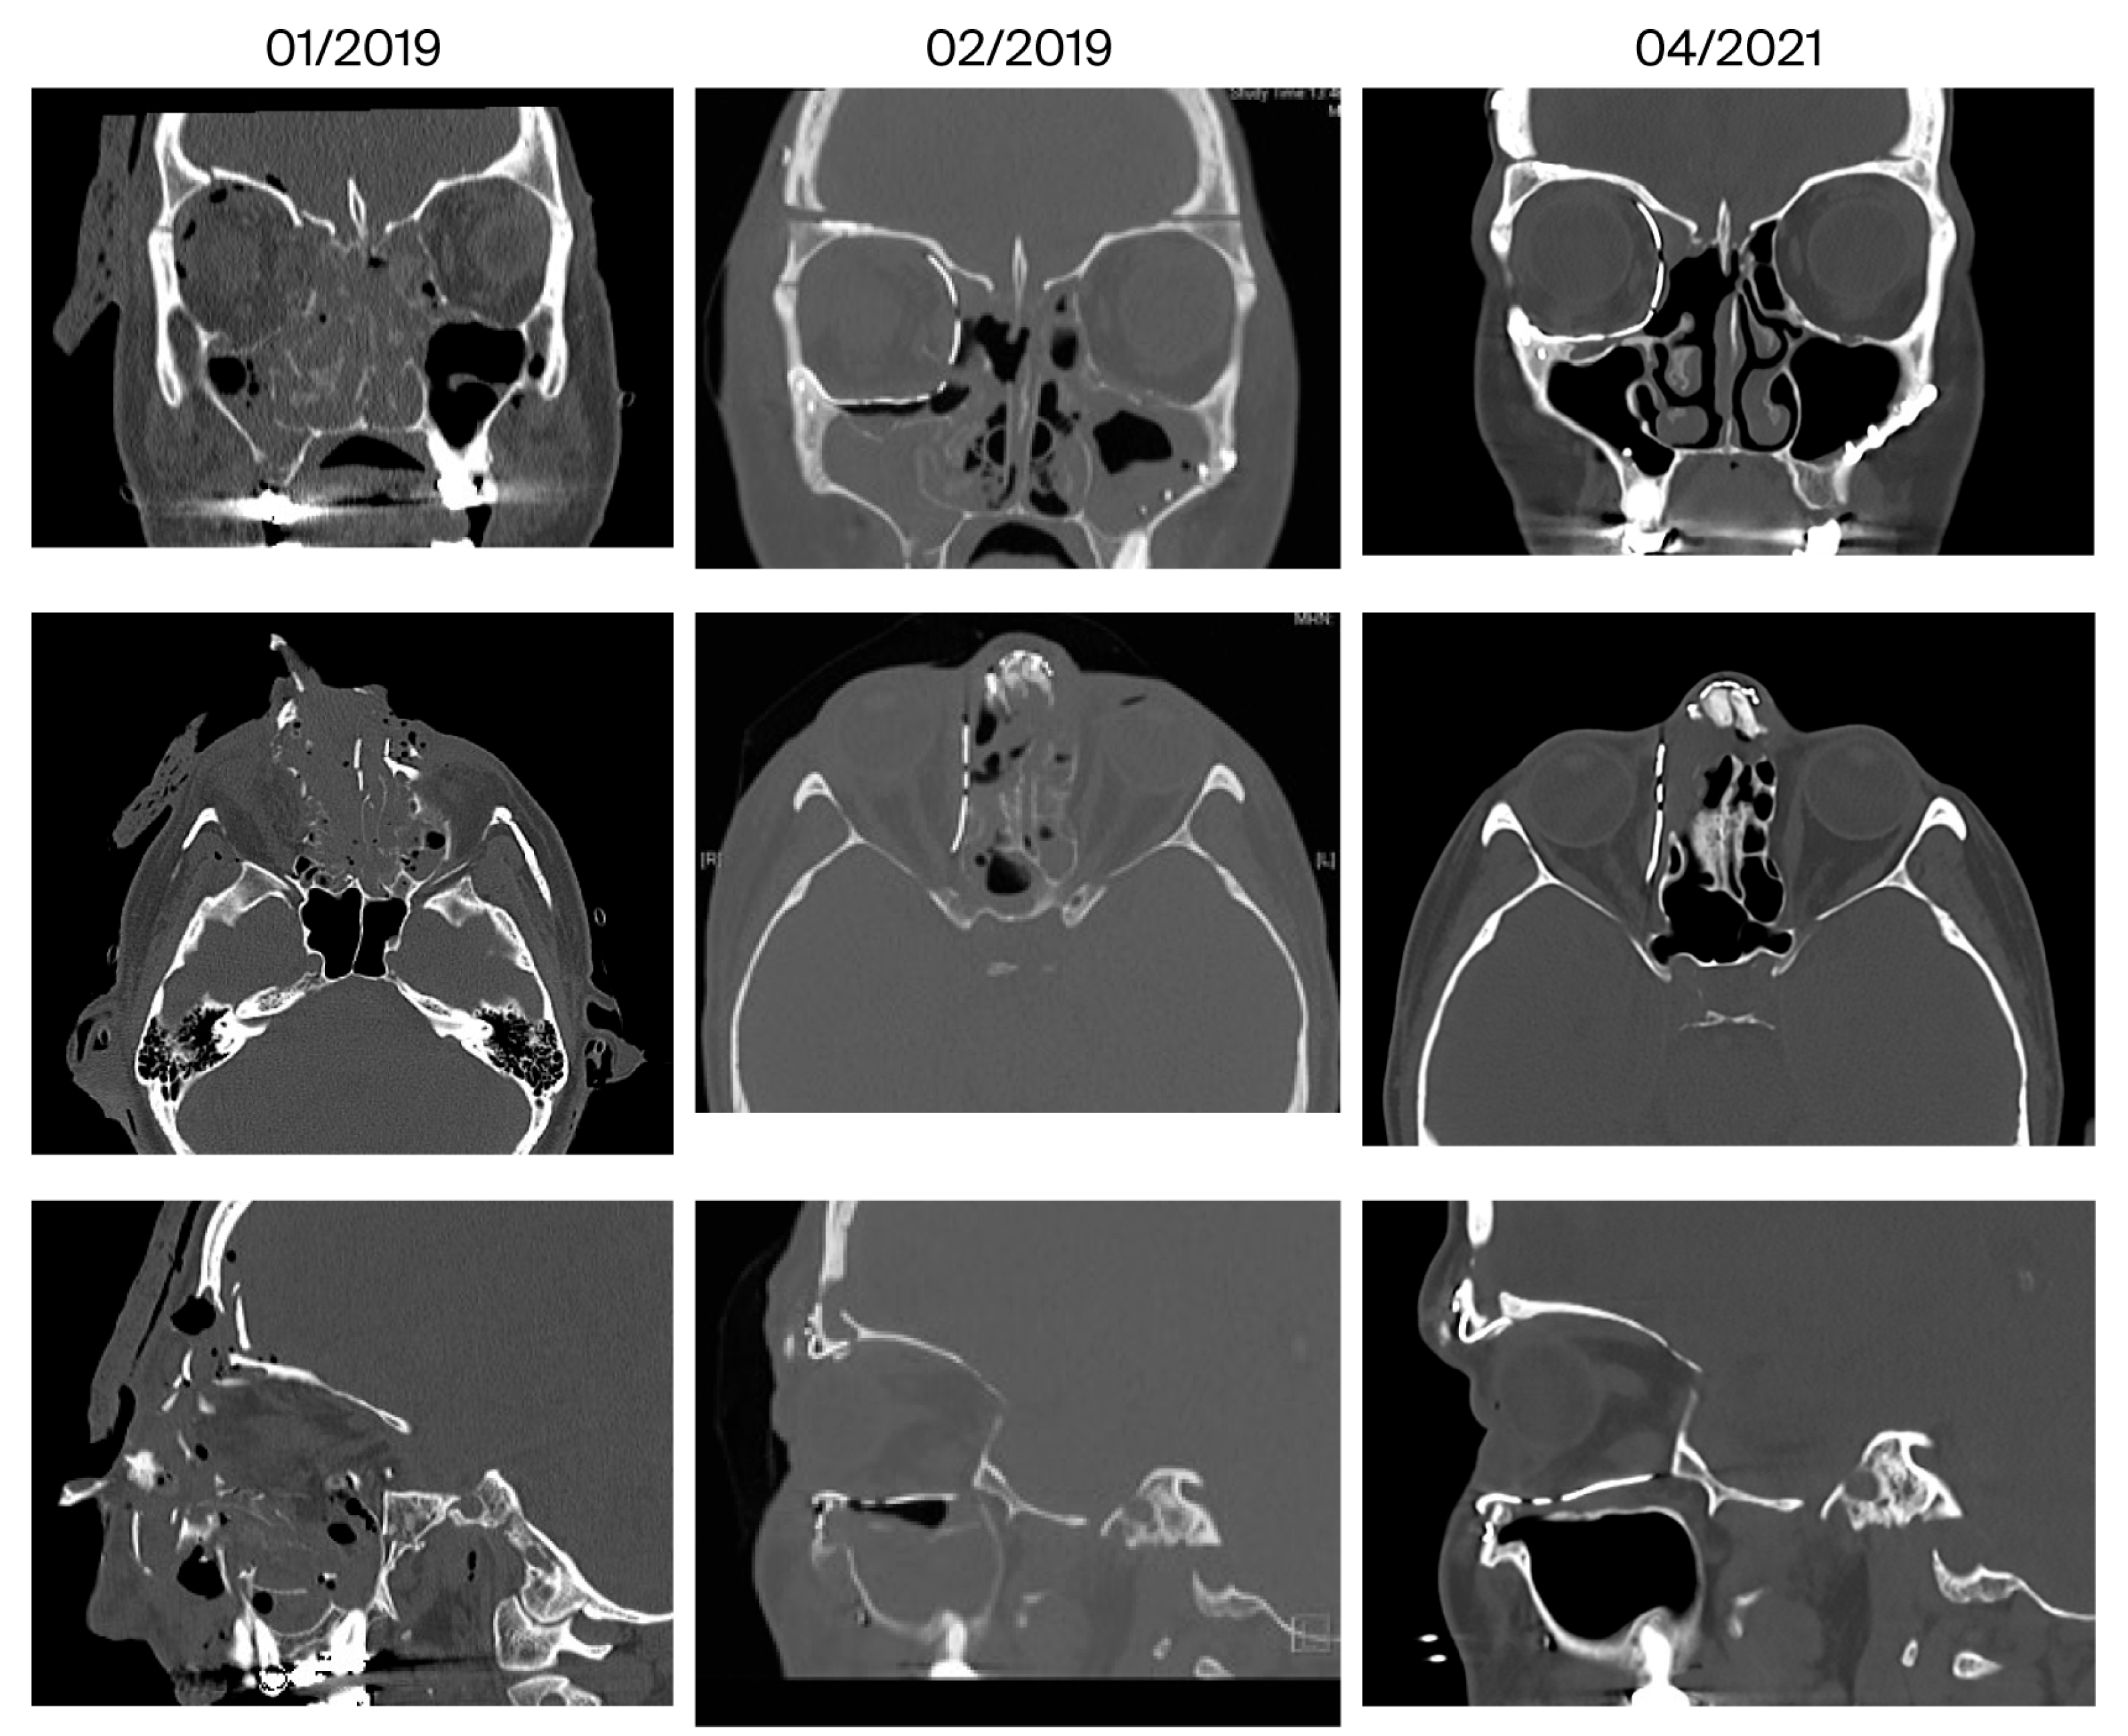

| 9 | February 2019 April 2021 (26 months) | Asymmetry, telecanthus on the right, scars in the nasal region | Yes | 5/5 | No | Ethmoidal | Yes |

| 10 | March 2020 January 2022 (22 months) | Anosmia, migraine | Mucosal swelling | 3/5 | No | Ethmoidal | Yes |

| 11 | December 2023 February 2025 (14 months) | Infraorbital hypesthesia | No | 6/3 | Yes | No | Yes |